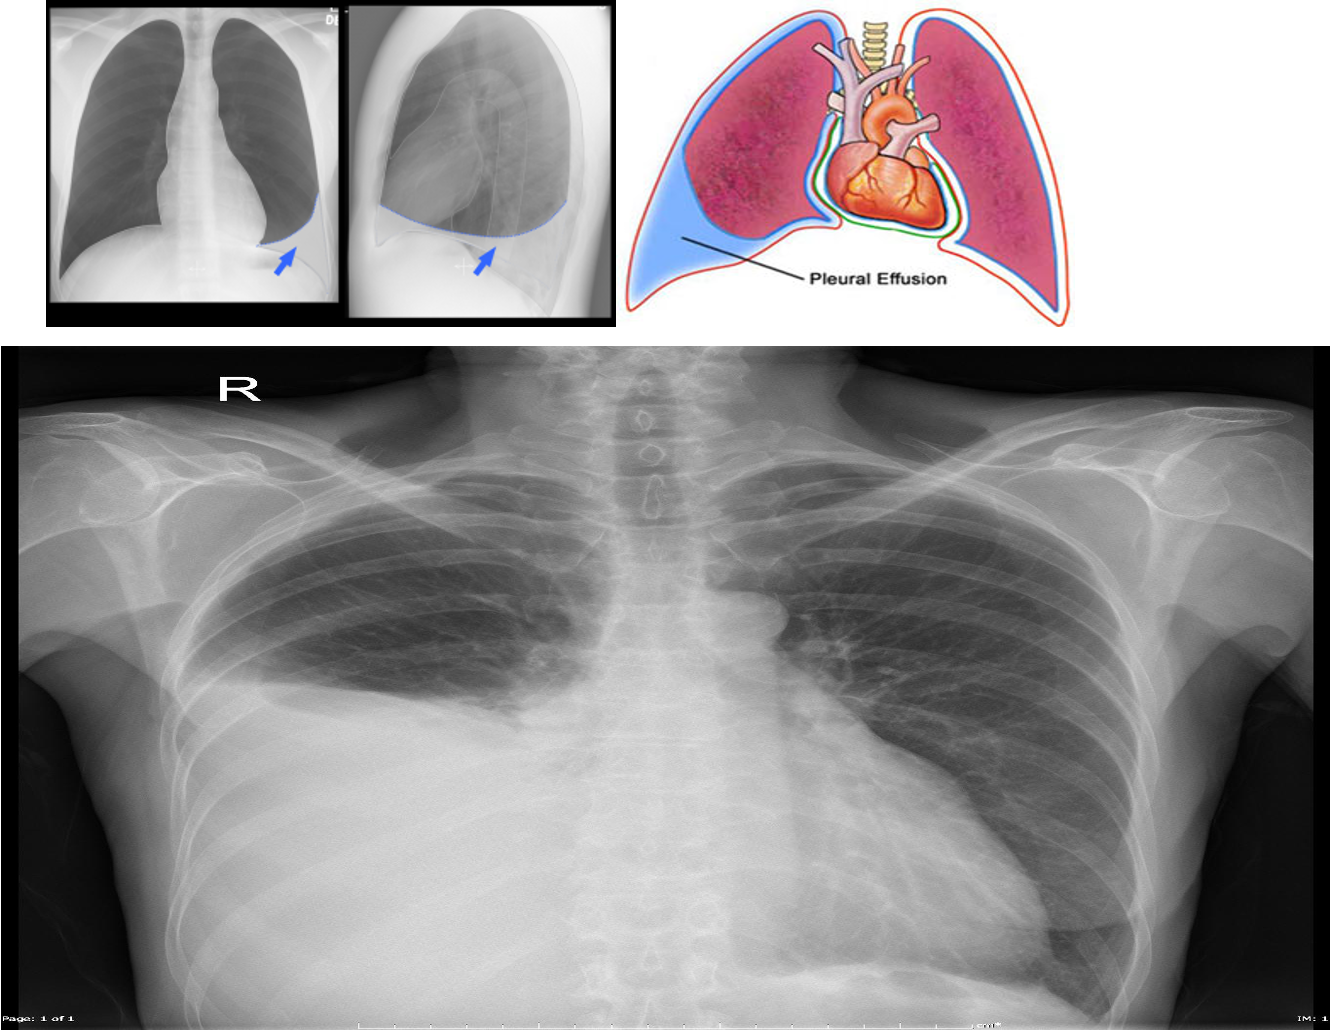

Imaging to confirm the diagnosis:

Chest X-ray: Lateral decubitus view (most sensitive): > 200 ml.

- Unilateral blunting of the costophrenic angle

- Homogeneous density with a meniscus-shaped margin (meniscus sign)

- Complete opacification of the lung (Large effusion) and Mediastinal shift and tracheal deviation.